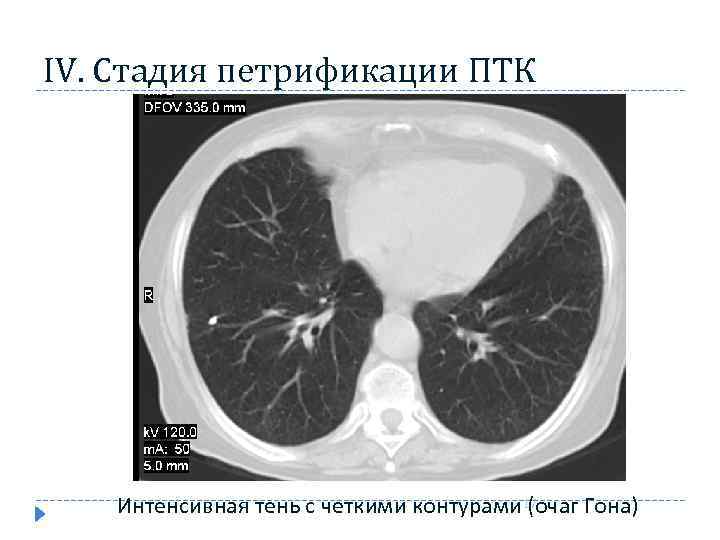

IV. Стадия петрификации ПТК 17 Интенсивная тень с четкими контурами (очаг Гона)

IV. Стадия петрификации ПТК 17 Интенсивная тень с четкими контурами (очаг Гона)

Стадия кальцинации очагов при ПТК характерно формирование в лёгочной ткани высокоинтенсивной очаговой тени с четкими контурами (очаг Гона) и включениями высокой плотности (кальцинатов) в регионарных лимфатических узлах 18

Стадия кальцинации очагов при ПТК характерно формирование в лёгочной ткани высокоинтенсивной очаговой тени с четкими контурами (очаг Гона) и включениями высокой плотности (кальцинатов) в регионарных лимфатических узлах 18